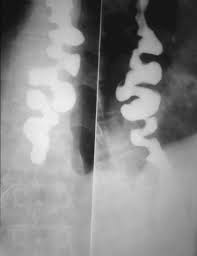

Barium swallow definition x ray. Fluoroscopy is often used during a barium swallow test. This series looks at your esophagus stomach and the first part of the small intestine duodenum. The progress of the barium is followed radiographically to detect filling defects e g places where a normal outline of barium should be seen. A test that involves filling the esophagus stomach and small intestines with a barium solution in preparation for an x ray to define the anatomy of the upper digestive tract.

Barium sulfate is a metallic compound that shows up on x rays and is used to help see abnormalities in the esophagus and stomach. A barium swallow is a test that may be used to determine the cause of painful swallowing difficulty with swallowing abdominal pain bloodstained vomit or unexplained weight loss. Upper gi barium swallow choose which type of a calculation. When taking the test you drink a preparation containing this solution.

Fluoroscopy is a kind of x ray movie why is a swallow test done. A barium swallow is a special type of x ray test that helps your doctor take a close look at the back of your mouth and throat known as the pharynx and the tube that extends from the back of the.